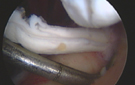

Im Rahmen einer Schulterarthroskopie erfolgt eine gezielte am Beschwerdebild und den bildgebenden Befunden orientierte Therapie.

Arthroskopisch wird der gereizte Schleimbeutel entfernt und die knöcherne Enge, ausgehend vom Schulterdach, wird erweitert. Mit Hilfe von speziellen Op-Instrumenten werden auch die knöchernen Anbauten im Bereich des Schultereckgelenkes entfernt bis ausreichend Platz geschaffen wurde.

Im Rahmen der von uns durchgeführten Schulterarthroskopie erfolgt sowohl eine symptomatische als auch eine ursachenorientierte Therapie.

Arthroskopisch wird das Kalkdepot entleert, der gereizte Schleimbeutel entfernt und die Enge, ausgehend vom Schulterdach, abgetragen. Mit Hilfe von speziellen Op-Instrumenten werden auch die knöchernen Anbauten im Bereich des Schultereckgelenkes entfernt bis ausreichend Platz geschaffen wurde.